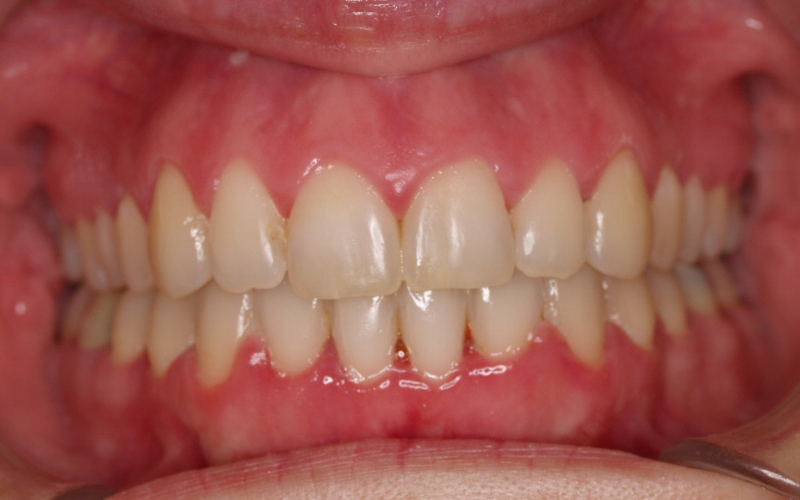

Premolar mandibular incluido + fenestración

45 incluido

Radiografía de final de tratamiento